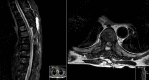

Brown-Séquard syndrome (BSS) is a rare neurological condition caused by a hemi-lesion of the spinal cord and was first described in the 1800s. BSS is characterized by an ipsilateral absence of motor control and discriminatory/proprioceptive/vibratory sensation at and below the spinal level involved, associated with loss of contralateral temperature and pain sensation a couple of vertebral segments below the lesion. BSS is commonly associated with trauma, but can also be iatrogenic. The authors report a case of a patient who presented with neoplastic dorsal spinal cord compression and developed a BSS after surgical decompression and review of the literature of postoperative BSS cases.